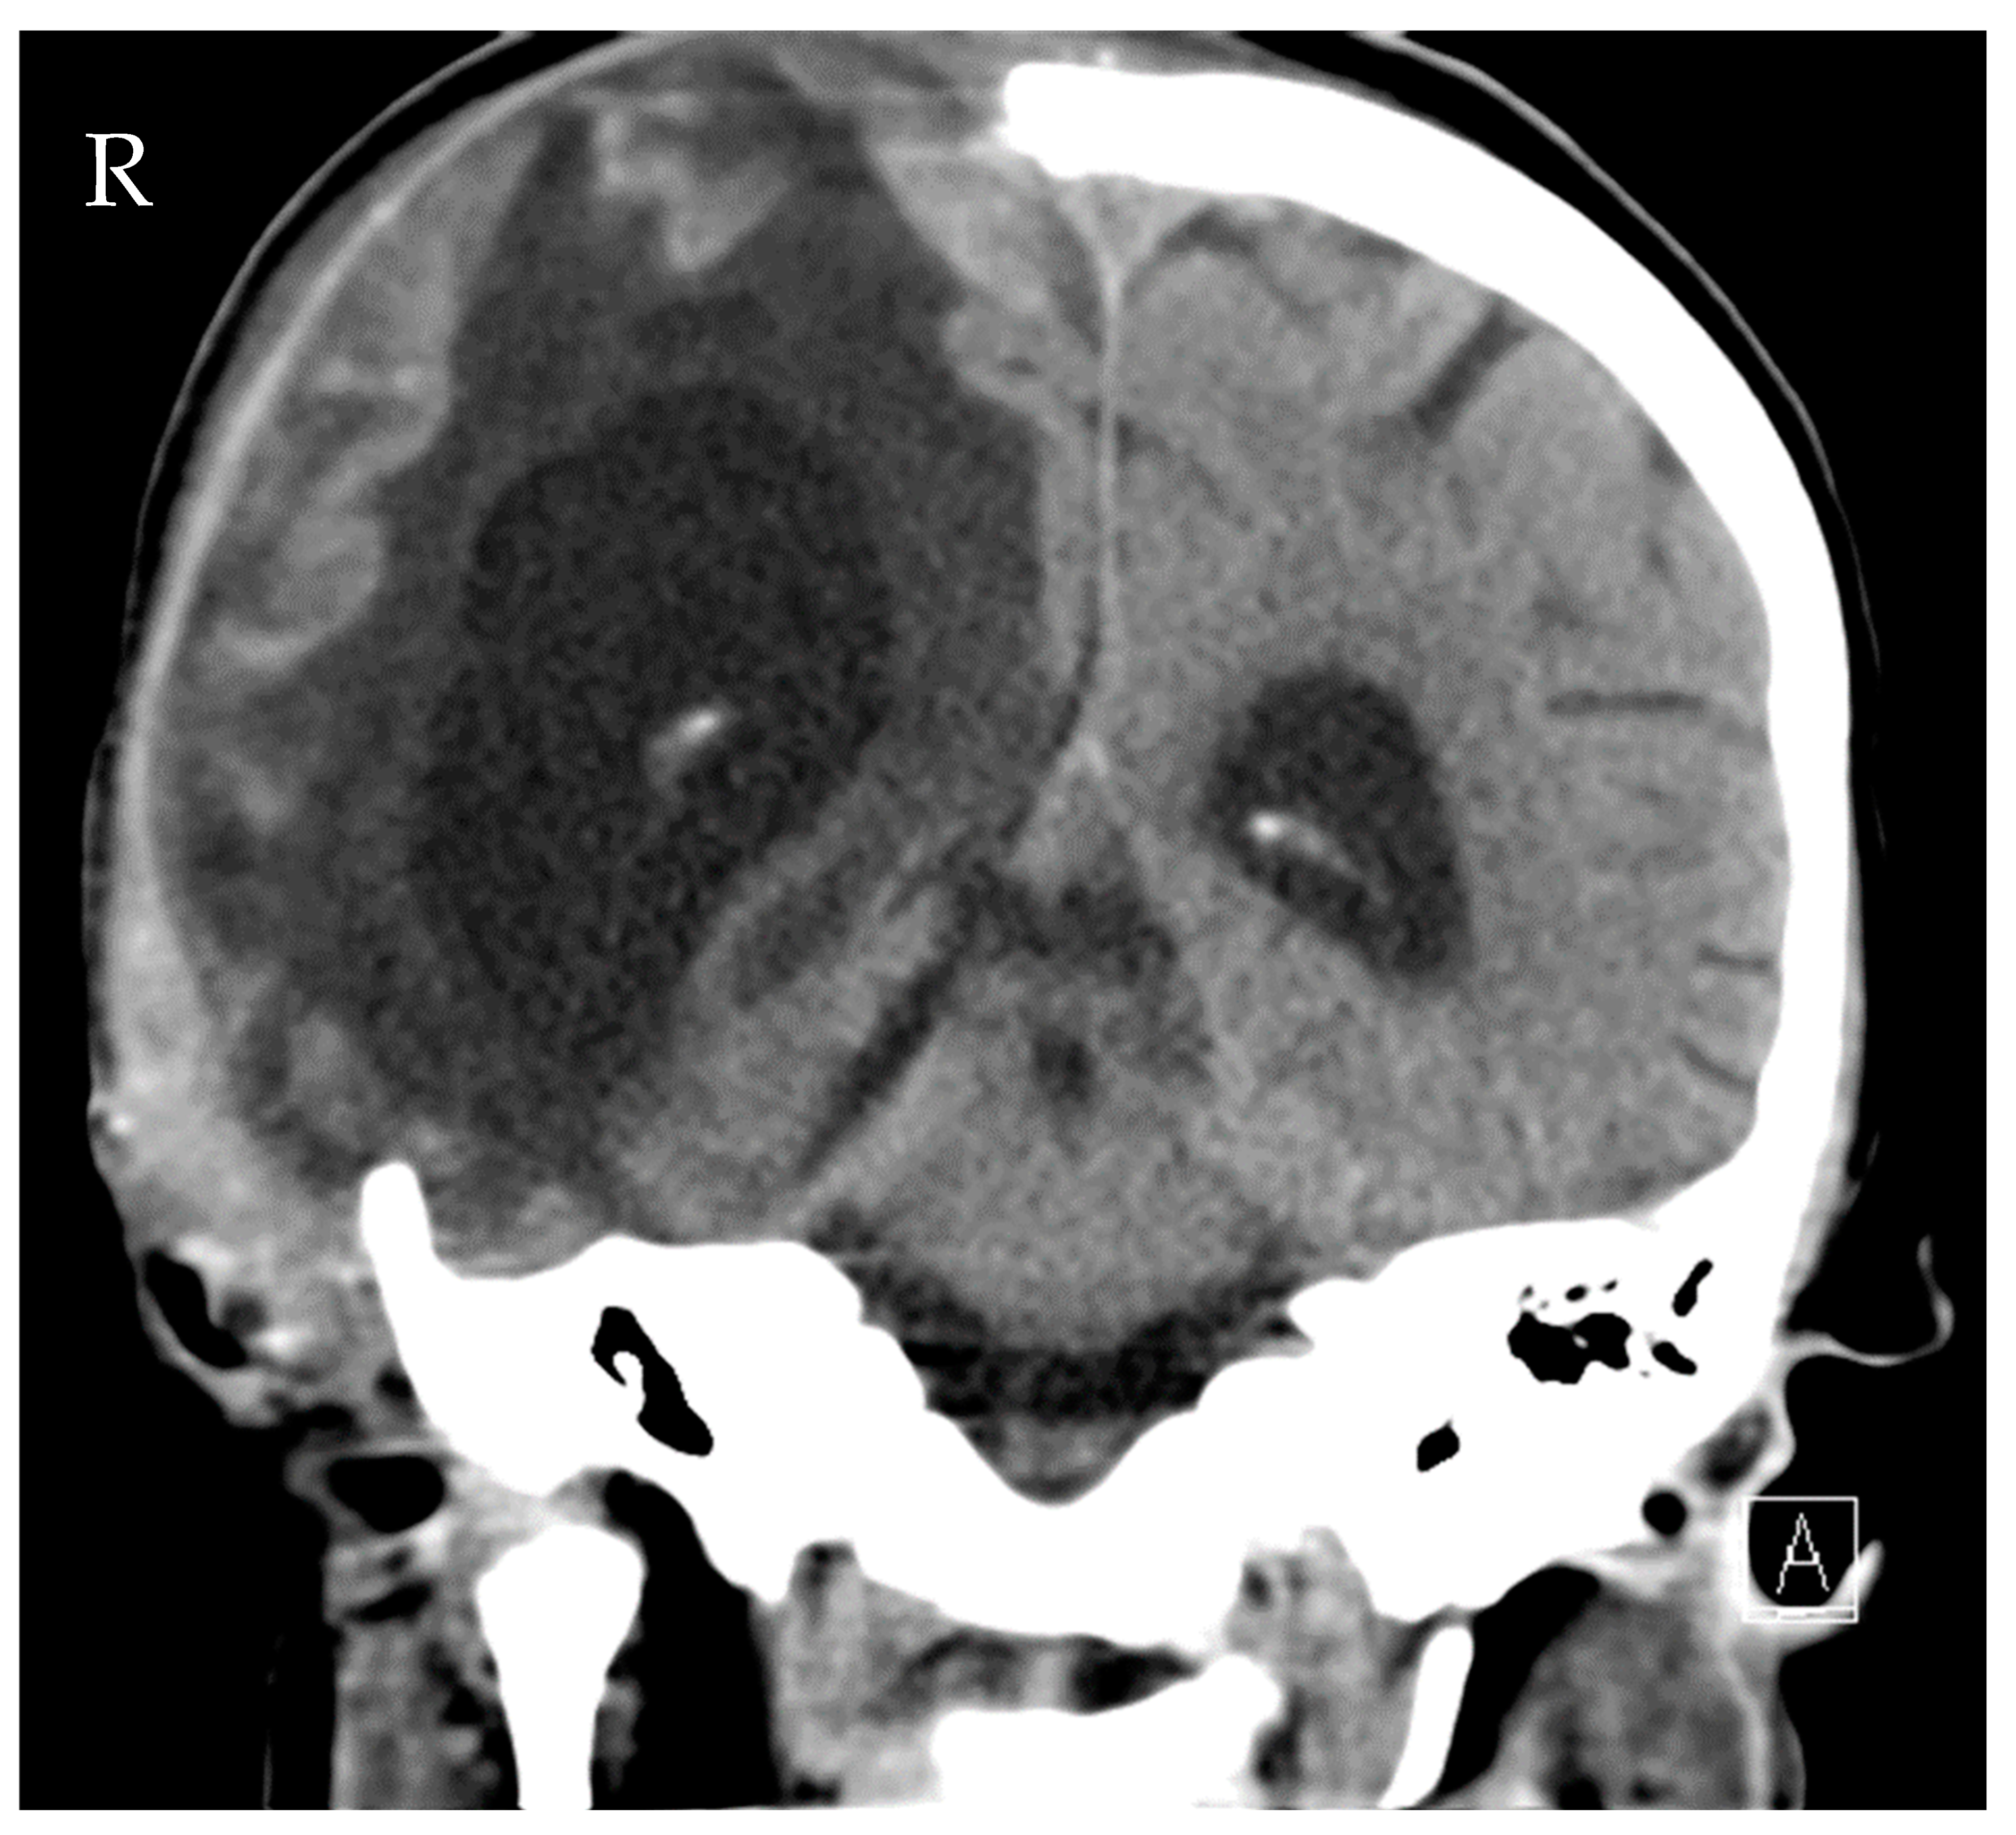

2. Case Presentation